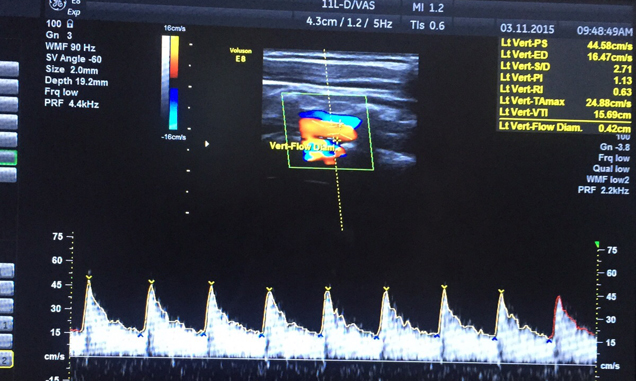

Peşəkar Radioloq Dr.Arzu Cəfərova ekstrakranial və aşağı,yuxarı ətrafların doppler müayinəsini həyata keçirir və bildirir ki, Dopplerometriya gələcək ananın və onun körpəsi arasında gedən qan dövranını öyrənən metodlarından biridir.Son illərdə bu metod hamiləliyin ikinci yarısında (20 həftədən sonra) geniş istifadə etməklə yanaşı həm də erkən müddətlərdə (11-14 həftə arası) məsələn preeklampsiya risk qrupunda olan hamilə qadınlarda üzə çıxardılması üçün istifadə edilir.Bu müayinə nəticəsində körpənin ürəyinin sağlamlığı, ürək döyüntüsü, həmçinin, onun müxtəlif orqanlarının nə dərəcədə qanla təchiz edilməsi haqqında məlumat əldə etmək mümkündür.Öz peşəsinin mütəxəssisi,Dr.Arzu Cəfərova bildirir ki,məhz dopplerin sayəsində ciftin fəaliyyətinin azlığını, göbək ciyəsinin boynuna dolanmasını və ya dölün hipoksiyasını təyin etmək olar.